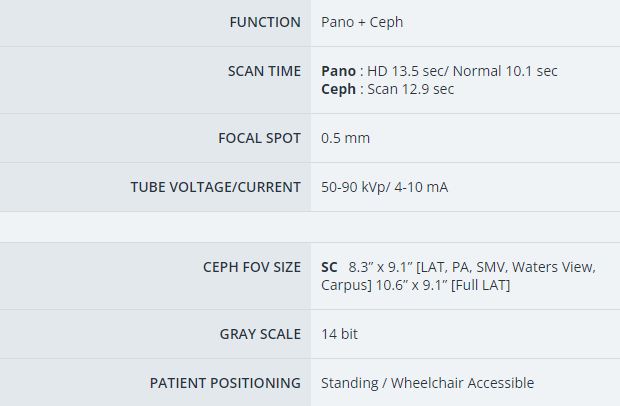

- Products Model: VAT-CBCT16

- Product Brand: Vatech America

Vatech A9 CBCT

The 'A9' is designed for dental clinics wanting to expand into high-value treatments like orthodontics and implant surgery. Vatech created the 'A9' to make CT technology more affordable for clinics, helping them manage the high costs. It also meets the growing demand as more clinics adopt CT technology.

The A9 provides high quality panoramic and CBCT images by combining image processing and accumulated experience in dental imaging from Vatech's image clarity expertise. This will increase your diagnostic accuracy for improved treatment planning and patient satisfaction.